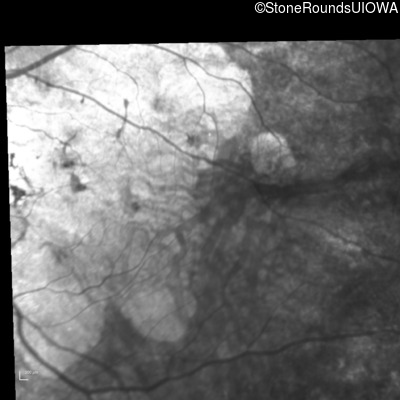

Infrared Fundus Photograph - Left - 20/200

Exemplar